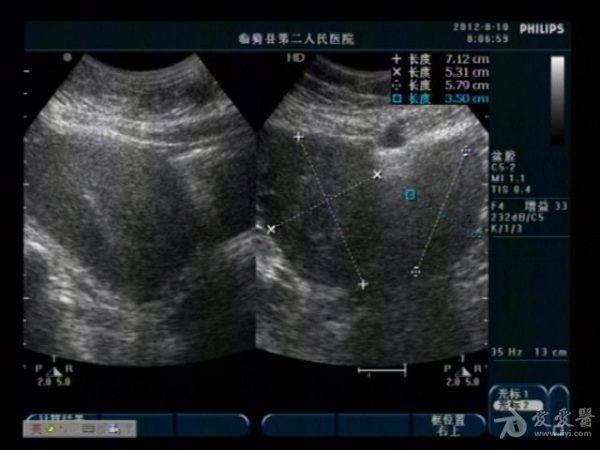

典型双子宫图像

前几天,我们科来了一位老病号,一年前剖腹产患者。当时手术证实“双子宫”今天超声图像可见一大一小两个子宫,右侧较大拟诊“子宫内膜异位症”。患者有经期腹痛史。

患者今年29岁,现生有一孩,就是剖宫产那个孩子。具体是那个子宫患者也不清楚,因在外地做的手术我们未能得到准确资料。患者近几个月来有明显的痛经史